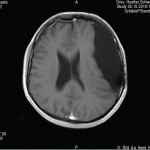

Ich stell euch hier noch eine kleine Galerie rein mit den neuesten Bildern. Ich denke es ist unübersehbar, dass das Ding gewachsen ist, außerdem mir meine komplette Hirnmittelline verschiebt und immer mehr Rücklagerung bekommt und Richtung Hirnsteuerungszentrum drückt. Meine häufiger auftretenden Stürze und Koordinationsprobleme werden also in naher Zukunft sicherlich nicht weniger werden und mein Doc und ich werden uns wohl auch zeitnah über eine weitere Klinik und eine mögliche weitere OP unterhalten müssen.